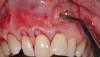

Fig 5. Preoperative. Class 2 Miller trauma-induced recession and associated tooth malposition.

Figure 5

Fig 6. Incision and flap relaxation. A vestibular incision subperiosteal technique-access incision (horizontal mucosal incision) allows for a full-thickness horizontal dissection. A total flap relaxation enables the clinician to avoid uncontrolled flap pressure on the APRF membranes and allows complete and passive coronal positioning of the soft tissues.

Figure 6